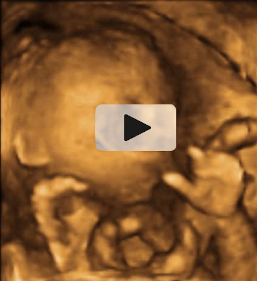

Las ecografías en 2D y en 3D en la semana 20 de embarazo permite diagnosticar algunas malformaciones congénitas fetales, como el labio leporino, que se visualiza en estas imágenes.

Labio leporino (*)

Visualización del mismo caso con ecografía 2D (izquierda) y con ecografía 3D (derecha). La imagen más evidente en la ecografía 3D hace más comprensible para los padres el alcance del problema.

Ecografía Embarazo 2D y 3D Semana 20 - MALFORMACIONES FETALES